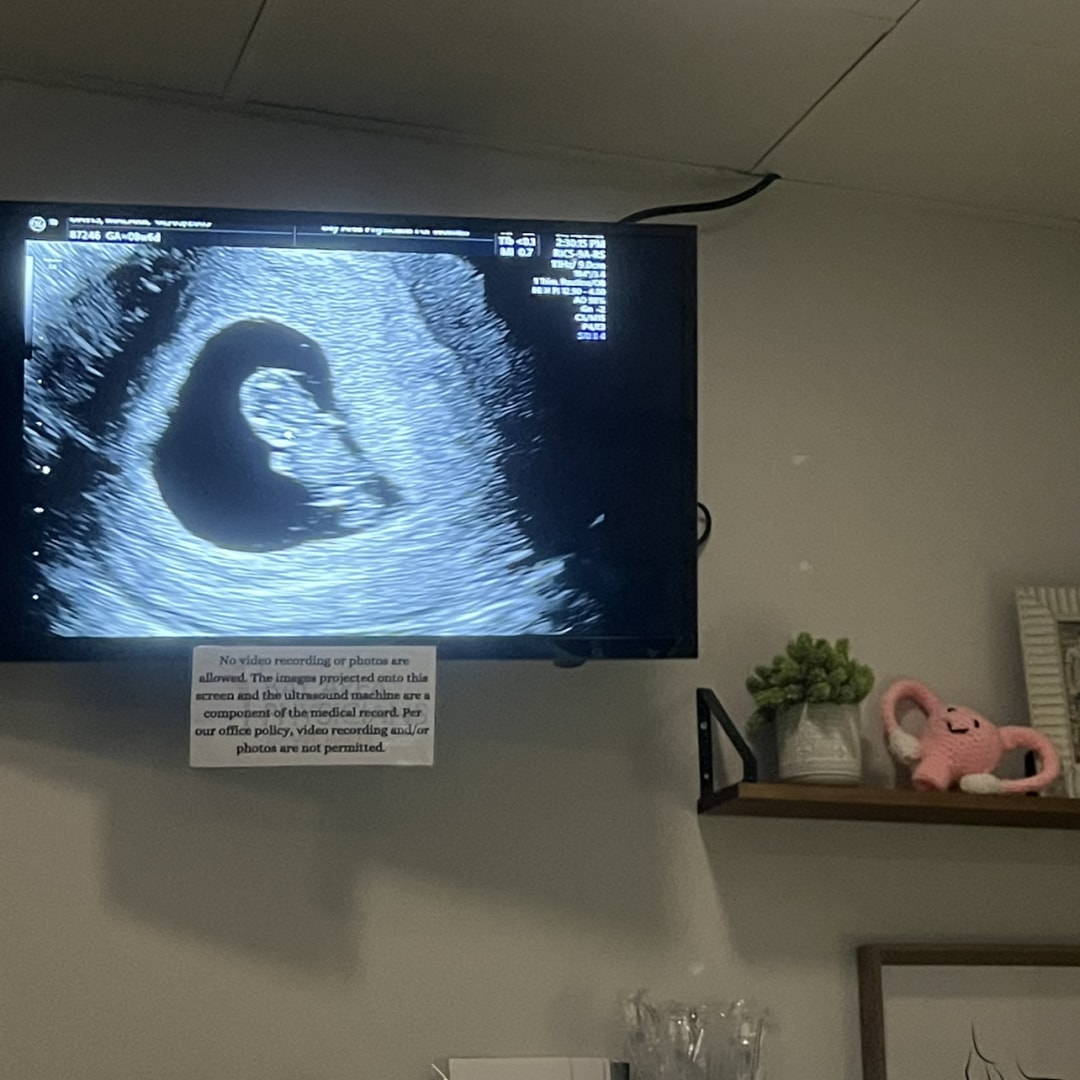

Matthew and I are so excited to welcome our sweet Aubrey Rose McIntosh in April 2026! 💕 We’ve put together a baby registry, and anything you’d like to contribute would mean the world to us.